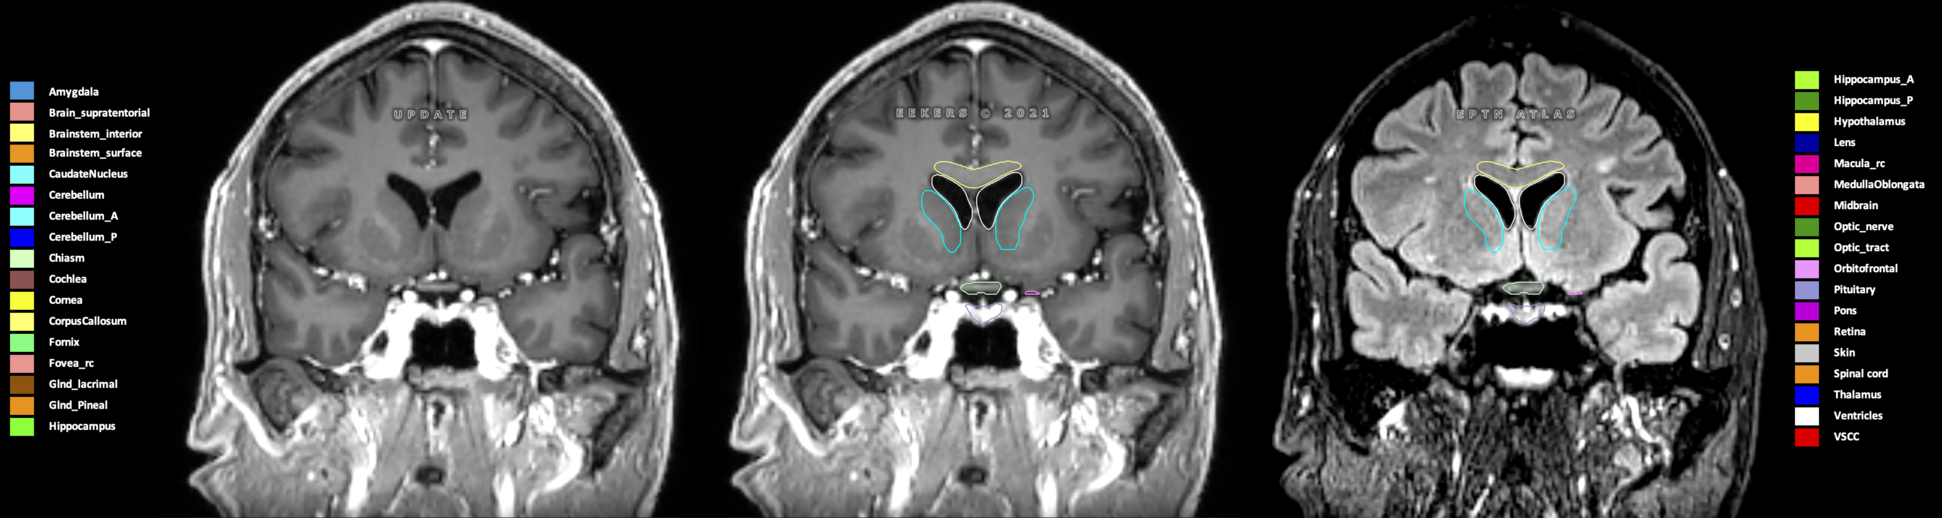

Eekers et al. have published an international neurological atlas for contouring of organs at risk in consensus with the European Particle Therapy Network (EPTN) in 2018 and an update in 2021. The purpose of this consensus atlas is to decrease inter- and intra-observer variability in delineating OARs relevant for neuro-oncology.

Included are all OARs known to be relevant for radiation-induced toxicity in neuro-oncology: brain, brainstem (midbrain, pons, medulla oblongata), chiasm, cerebellum (anterior & posterior), cochlea, cornea, hippocampus (anterior & posterior), hypothalamus, lens, lacrimal gland, optic nerve, pituitary, skin, and vestibular & semicircular canals. To further facilitate research on cognition, vision and radiological changes after irradiation of the brain, potential clinically-relevant OARs are included: amygdala, caudate nucleus, cerebellum (anterior & posterior), corpus callosum, fornix, macula, optic tract, orbitofrontal cortex, periventricular space (PVS), pineal gland, and thalamus.

Three-dimensional delineation of the 25 consensus OARs for neuro-oncology are shown on CT (WW/WL 120/40, 3000/600), 3T MR images, (T1Gd, T2FLAIR 1mm) and 7T MR (MP2RAGE 0.7 mm). All are presented in transversal, sagittal and coronal view.